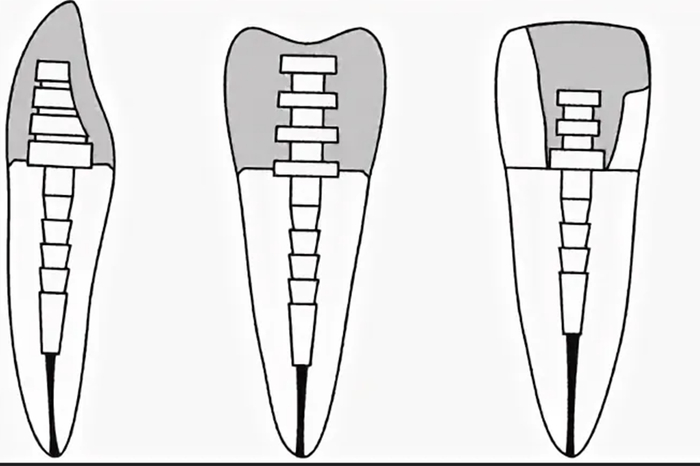

Изготавливают прямо во рту у пациента. Являются, пломбой на штифте, и называются модным словом «билд-ап», что по-буржуйски «наращивать». Зуб изолируется от слюны, запломбированный канал частично распломбирововается, туда сразу вставляют обработанный штифт со специальным пломбировочным материалов, после чего на штифте ваяется новая культя, которая обтачивается и покрывается коронкой. В обязательном порядке. Почему? Смотри тут

Так выглядит после обточки

А это схематично, чтобы вы поняли.

2) Непрямые конструкции.

Изготавливают по слепку в зуботехнической лаборатории. Представлены чаще всего культевыми вкладками (они же ШКВ, ЛКВ), где штифт и культевая часть являются одним целым.

Формируется полость и путь введения под вкладку, один из каналов распломбировывается на 1\2-2\3 длины корня, снимается слепок и отдается зубному технику.

Этот слепок отливается из гипса, из воска\выжигаемой пластмассы делается будущая вкладка и отдается литейщику. Литейщик отливает её из металла, техник малость обрабатывает, подгоняет и отдает врачу. Врач фиксирует вкладку в зуб с помощью цемента, потом всё это дело обтачивается и покрывается коронкой.